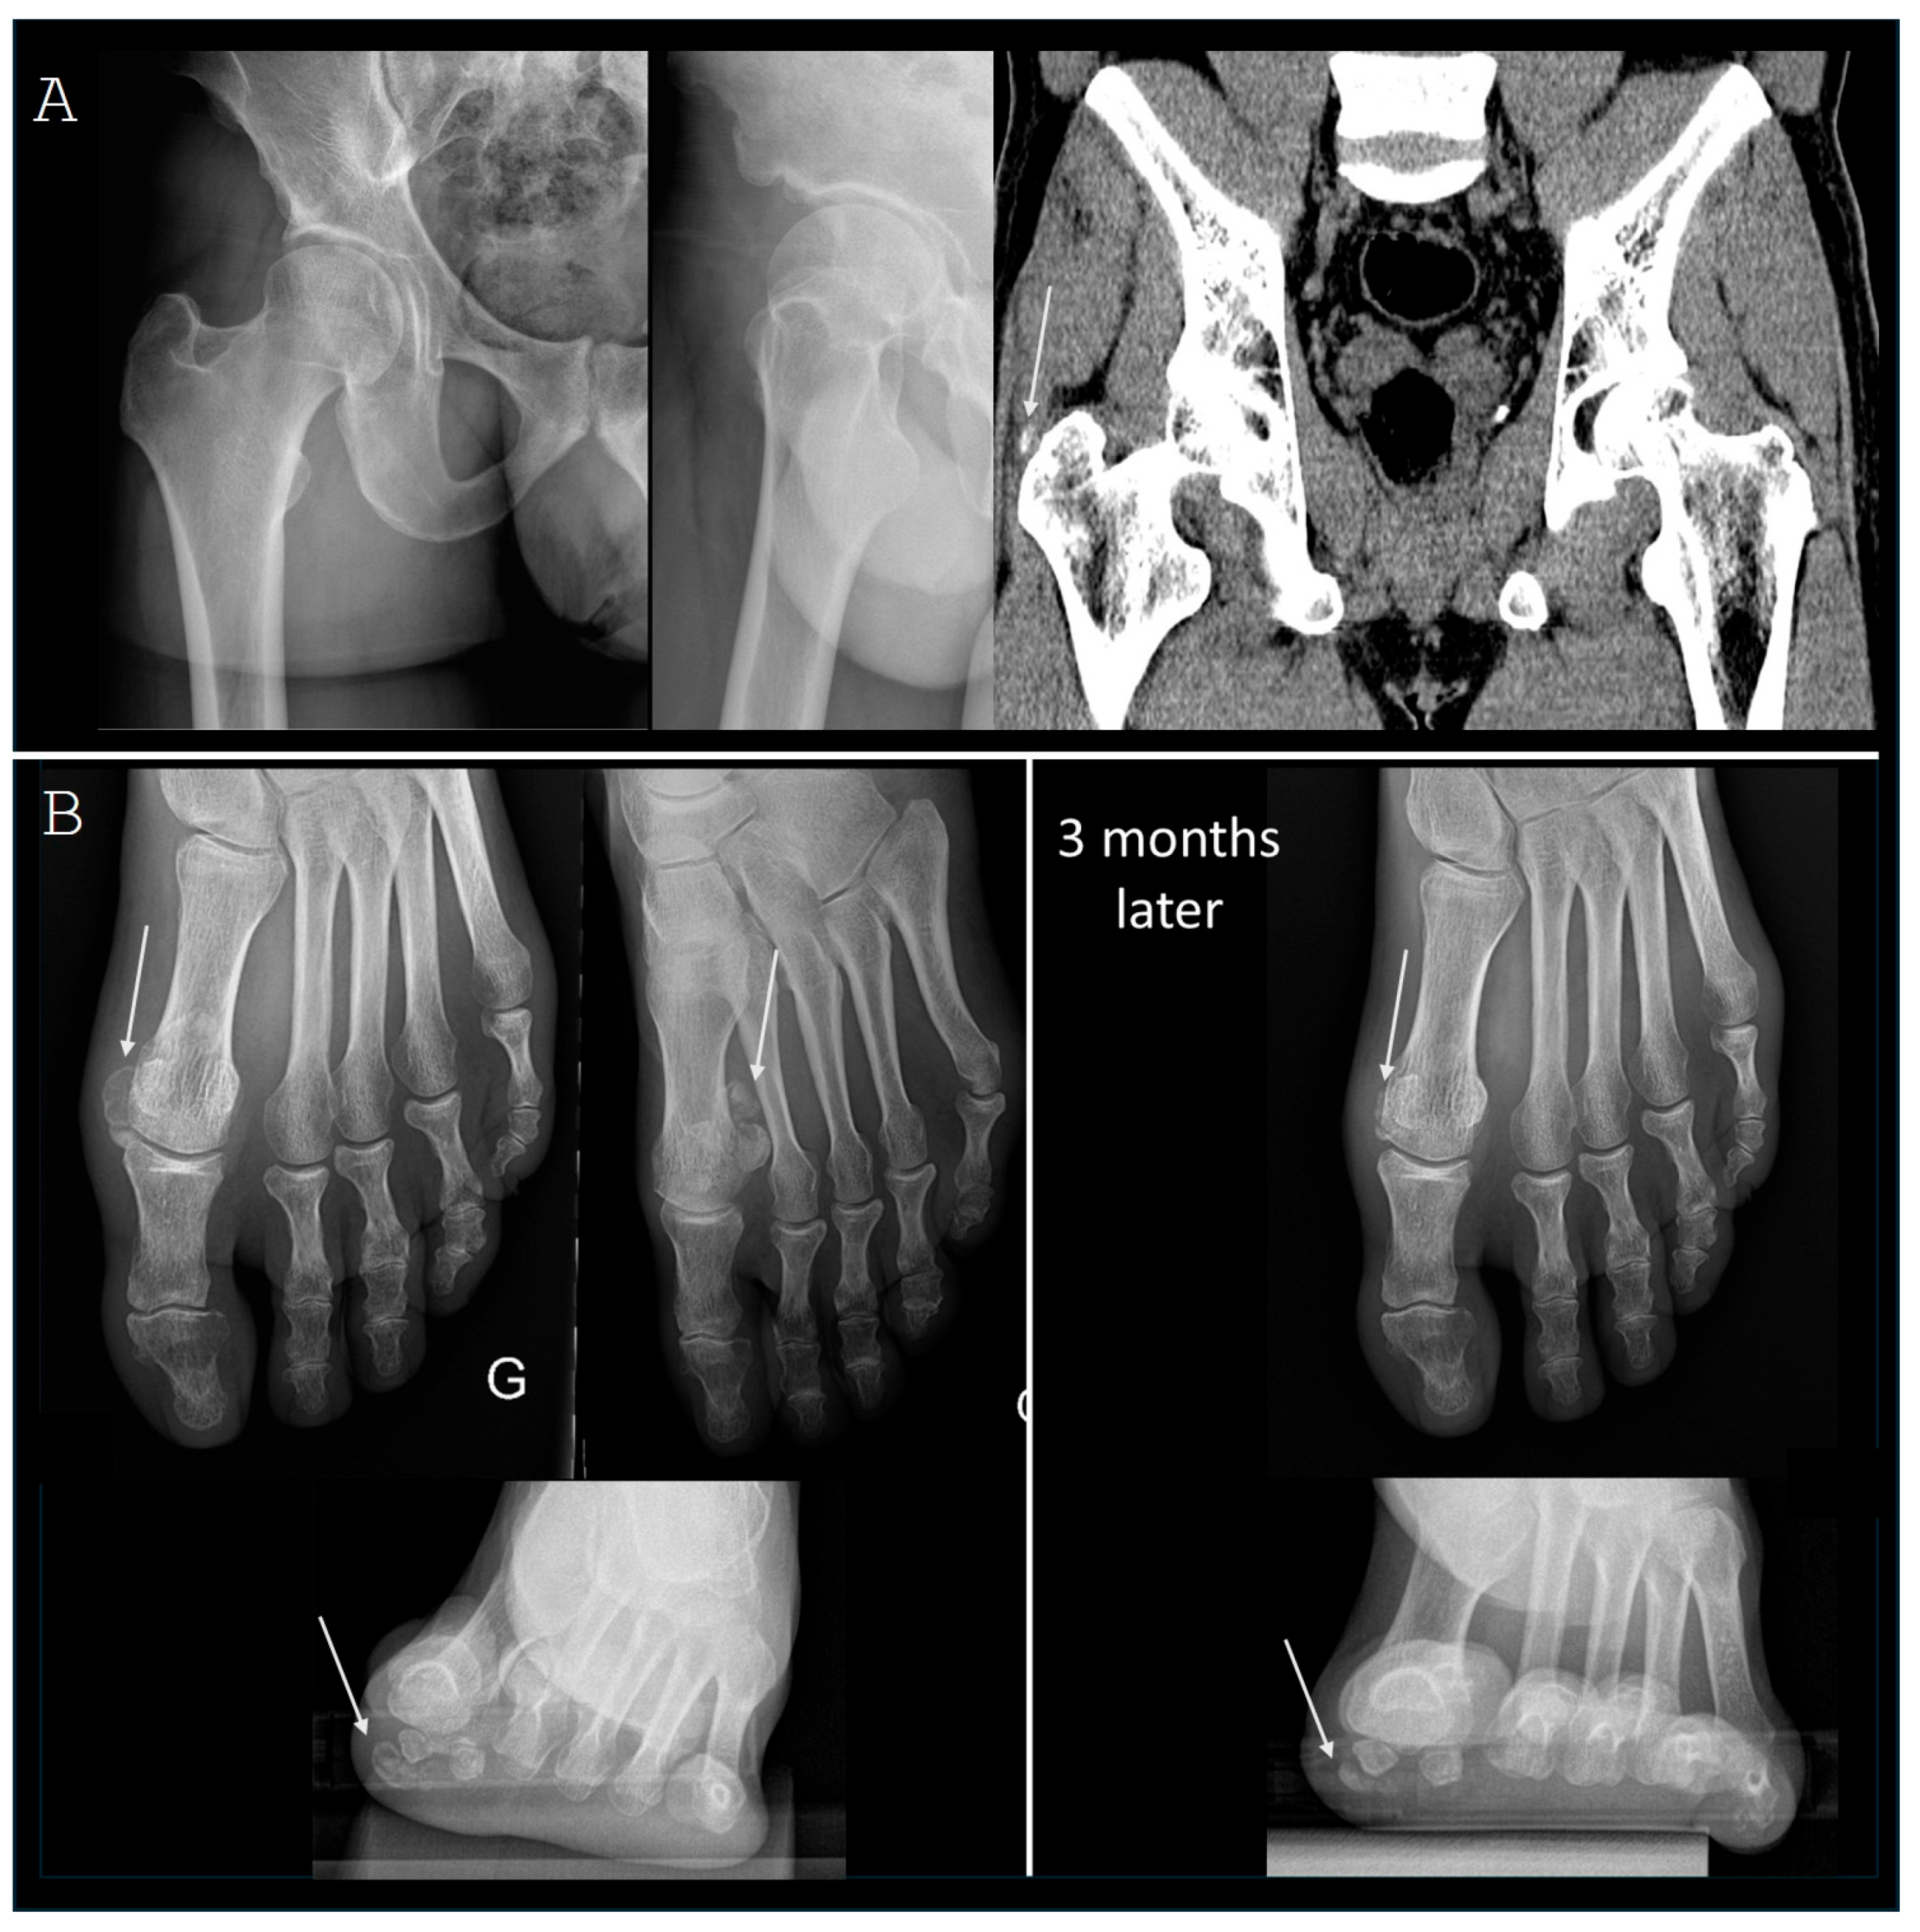

3.2. Lower Limb Involvement